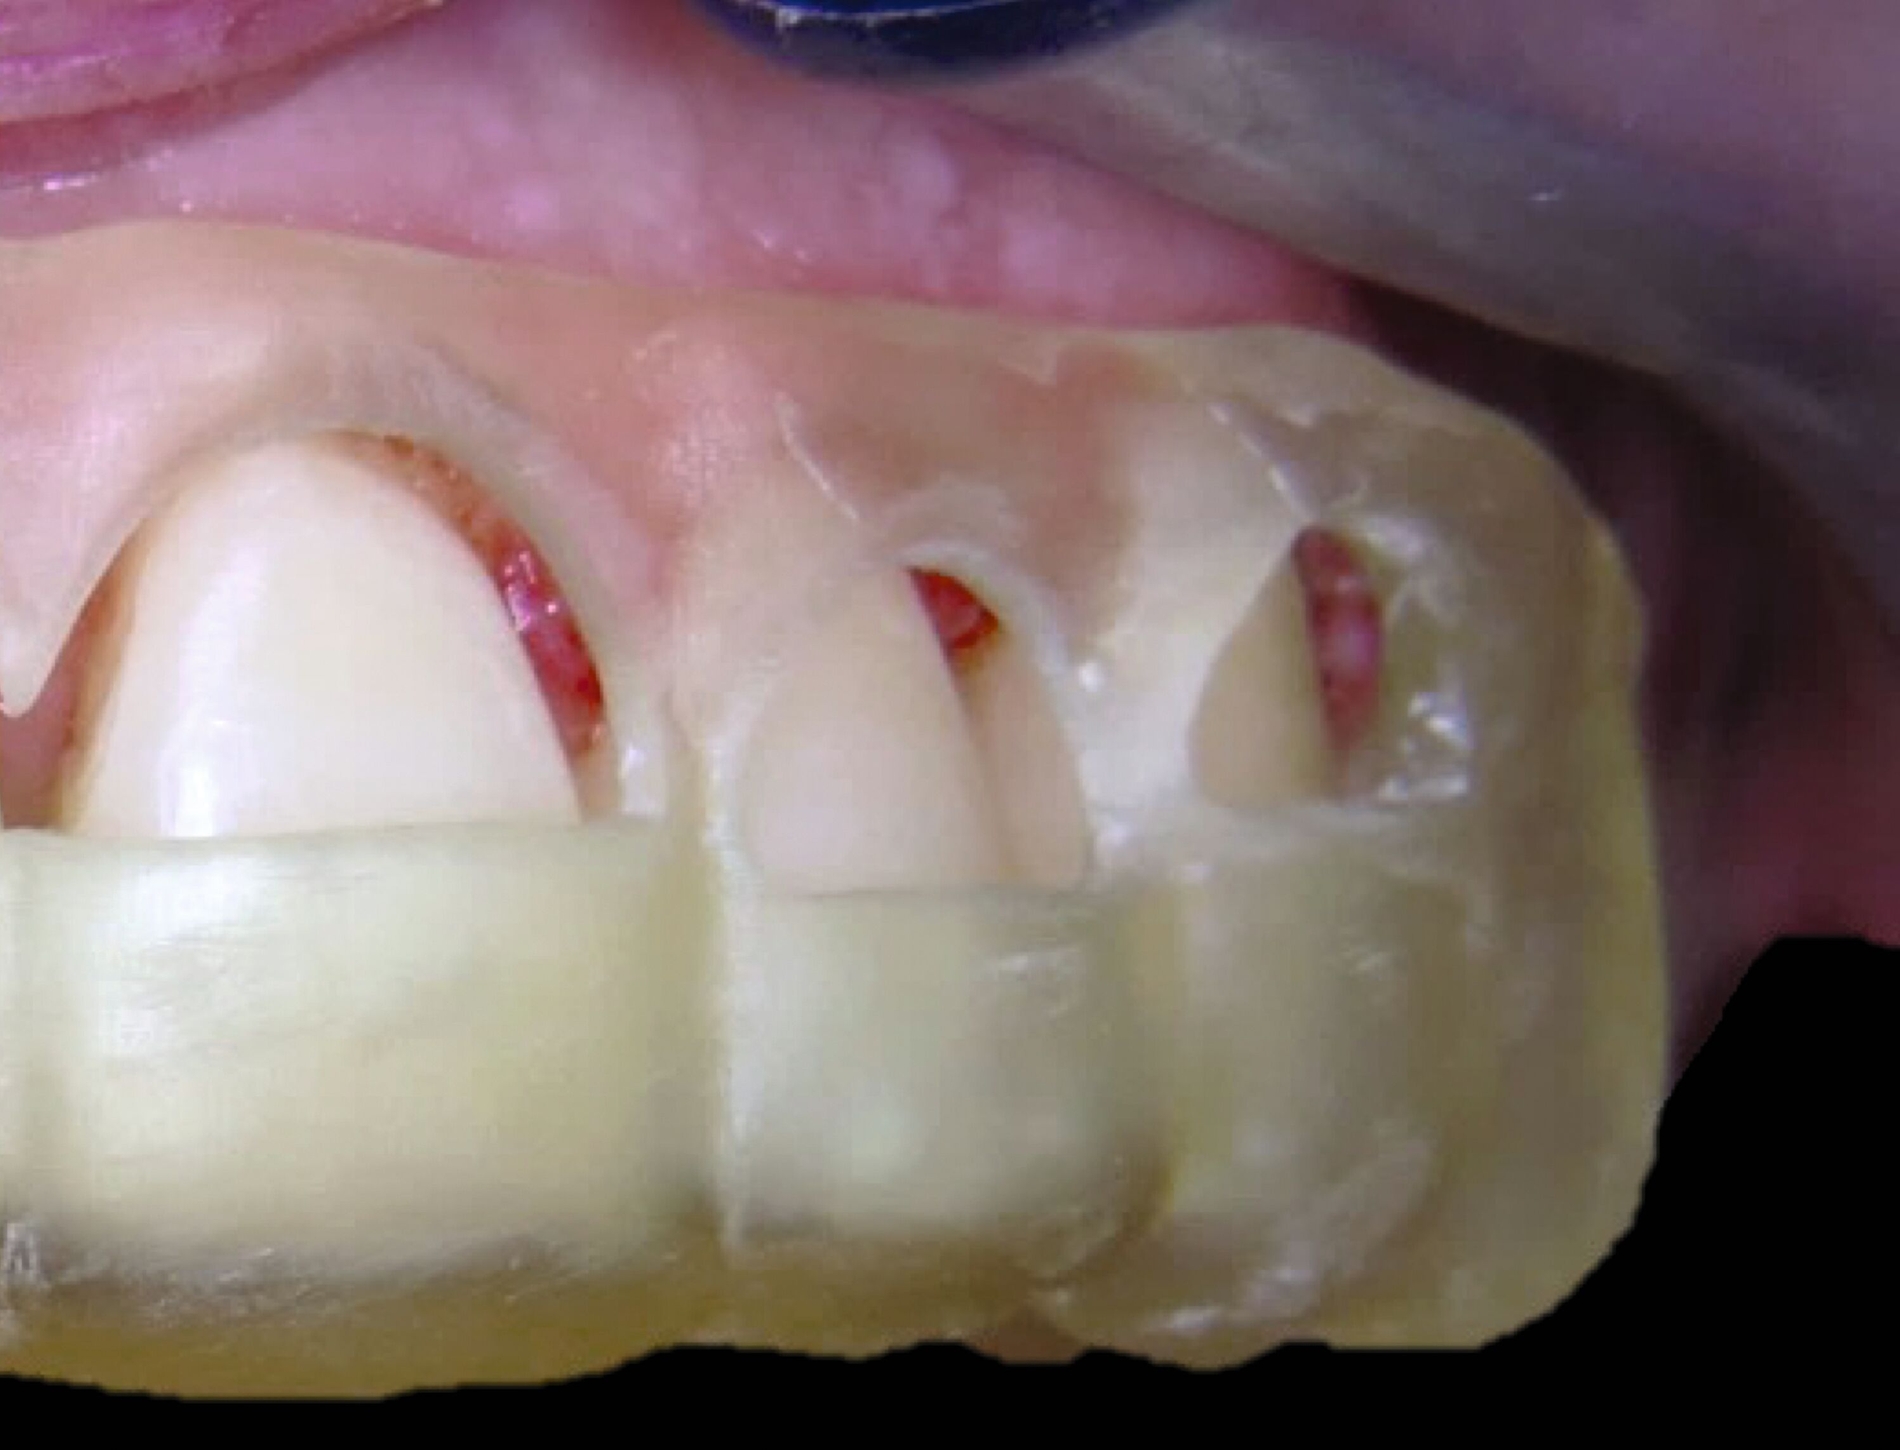

Weitere Beispiele beinhalten hochkomplexe Behandlungsfälle multipler Zahnanlagen. Während die Extraktionsentscheidung und Absprache mit dem/der chirurgisch tätigen Kollegen/in allein auf Basis der Bildgebung oft limitiert ist, erleichtern 3-D-gedruckte Modelle des segmentierten DVTs sowohl die Entscheidung als auch die Absprache und ermöglichen darüber hinaus eine genauere Planung des chirurgischen Vorgehens (Abbildung 6c). Gleiches betrifft parodontalchirurgische Eingriffe, in denen sogenannte „Cutting guides“ eine zuvor digital geplante Gingivektomie ermöglichen (Abbildung 6d). Im Bereich der Freilegung verlagerter Zähne können Schablonen dem/die chirurgisch tätigen Kollegen/in sowohl die Freilegung des Zahnes (Abbildung 6e) als auch die Anbringung eines Attachments (Abbildung 6f) erleichtern und dabei die kieferorthopädisch gewünschte Attachmentposition passgenau übertragen.